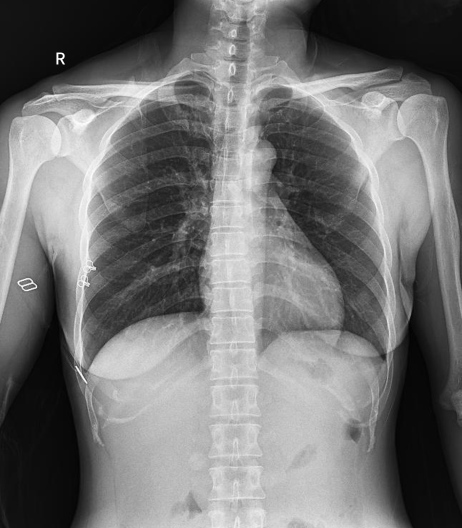

普利德醫療自主研發的新一代數字化X線透視攝影系統,可應用于DR攝影、數字透視、數字造影以及可視化精準DR拍片等多種臨床X線檢查領域。

球管傾斜攝影角度-45°~45°,滿足臨床各部位各角度的攝影需求。如:髕骨軸位、頸椎正位、骶尾椎、鼻竇瓦氏位、梅氏位等部位檢查。

拉伸自如:SID電動拉伸,最長可延伸至1.8米,滿足放射科室各種拍片距離的需求。如:GBZ 70-2015職業性塵肺病的診斷標準中對胸片拍片距離1.8米的要求。